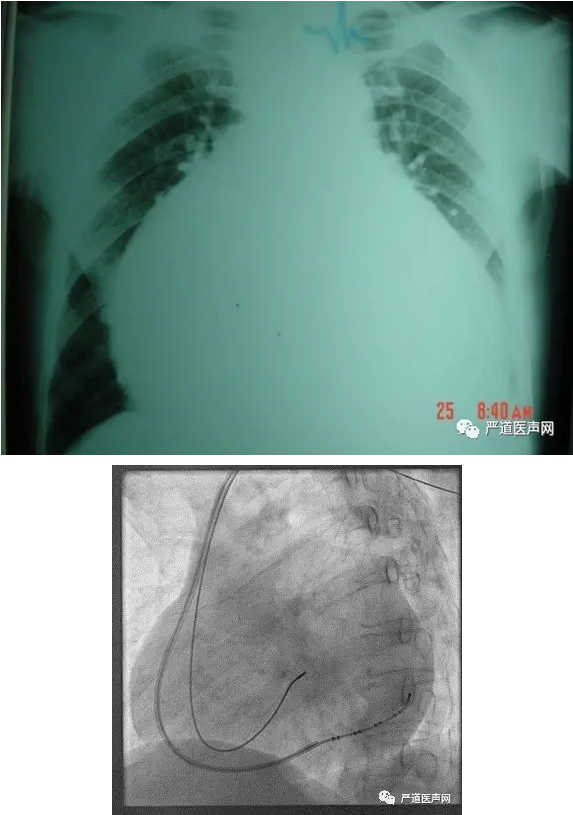

大右房

冠状窦口异常:大右房、高开口

● 1.Amplatz AL-3主要应用于巨大的右心房,可使内导管形成一个向上的成角进入冠状静脉窦开口

● 2.大弯度指引导管:主要应用于右房大、冠状静脉窦开口较高的患者;